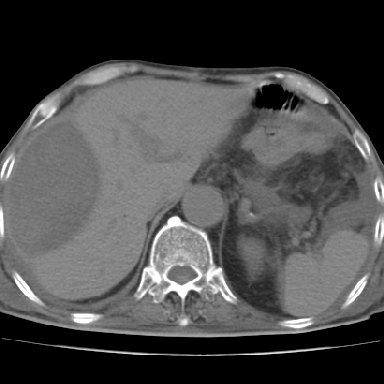

以下是引用chry3在2006-12-4 21:05:00的发言:[br]应该往上扫几层,我考虑膈下脓肿。[br]大家考虑:胃部手术怎会造成肝内脓肿,隔下脓肿到是会造成的

以下是引用dyqct在2006-12-4 19:54:00的发言:[br]考虑:1、肝包膜下脓肿;[br] 2、少量腹水;[br] 3、右侧少量胸膜腔积液。